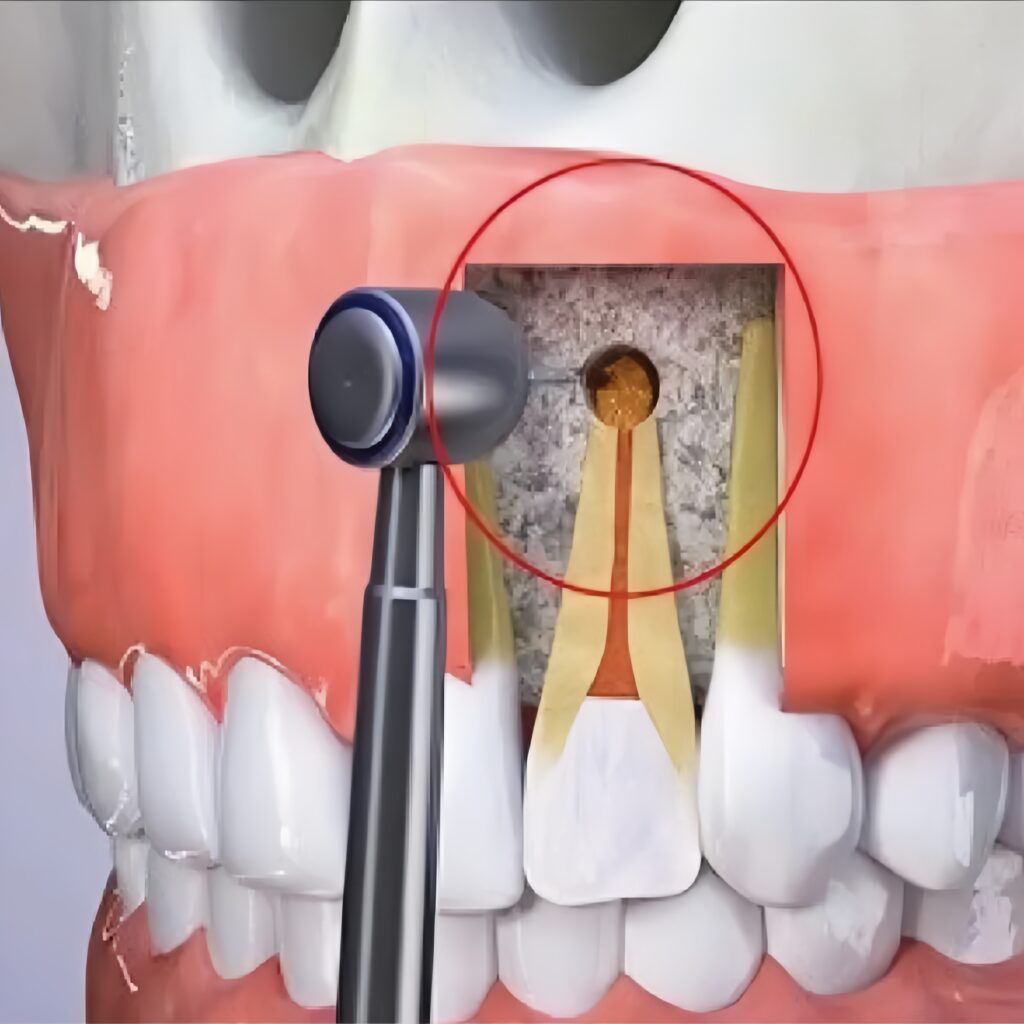

- 3. Gây tê, tiếp cận và cắt chóp chân răng: Trước khi bắt đầu quy trình, vùng cần điều trị sẽ được gây tê để đảm bảo bạn không cảm thấy đau hoặc khó chịu trong suốt quá trình điều trị. Bác sĩ sẽ tạo đường vào vị trí chóp răng bị nhiễm trùng, loại bỏ khoảng 2mm phần chóp răng, đồng thời làm sạch mô viêm xung quanh.

- 4. Trám ngược chóp răng và khâu đóng vết mổ: Sau khi vùng viêm đã được làm sạch, phần cuối của ống tủy sẽ được trám bít ngược lại bằng vật liệu chuyên dụng để ngăn chặn sự tái nhiễm trùng. Vết mổ sẽ được khâu đóng và lành lại trong vài tuần sau đó.